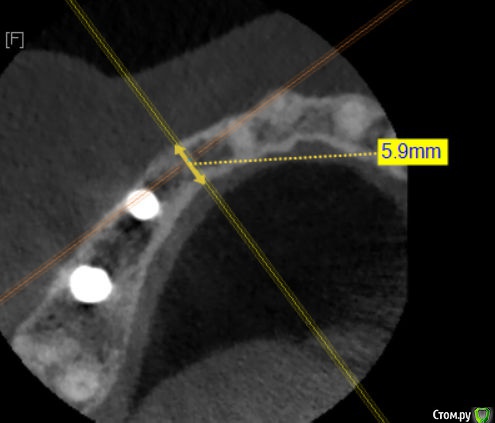

Kazankov.Egor Опубликовано 17 мая, 2018 Поделиться Опубликовано 17 мая, 2018 Господа ветераны, делать нкр или поставить винт 3.3+сст? Бояться ли в данном случае угла (в связи с функцией коронки)? Ссылка на комментарий

Nazim_NV86 Опубликовано 17 мая, 2018 Поделиться Опубликовано 17 мая, 2018 Главное вестибулярно кортикалку не испортить. 3.3-3.5 легко закрутится. Чуть расщепить можно, +1мм будет. Ссылка на комментарий

Evikrol Опубликовано 17 мая, 2018 Поделиться Опубликовано 17 мая, 2018 3,5 на 11,5 или 13 мм и заглубится + сст 3 Ссылка на комментарий

Kazankov.Egor Опубликовано 17 мая, 2018 Автор Поделиться Опубликовано 17 мая, 2018 Главное вестибулярно кортикалку не испортить. 3.3-3.5 легко закрутится. Чуть расщепить можно, +1мм будет.Распилы не делать вертикальные? Просто сделать горизонтальный по вершине гребня и расширить? Как в случае расщепа модифицируется протокол сверления? Планирую BL 3,3#13.Лучший ли выбор для такой ситуации? Ссылка на комментарий

Иван911 Опубликовано 18 мая, 2018 Поделиться Опубликовано 18 мая, 2018 Штрауман.3.3-10 blt берите, только roxolid! 3 Ссылка на комментарий